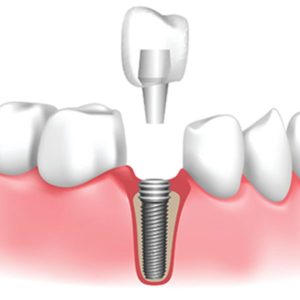

Trồng răng implant